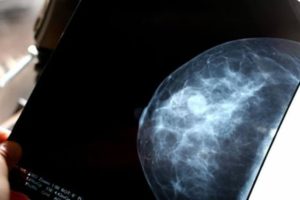

breast-scan_hero

AI Catches More Breast Cancers and Cuts Radiologist Workload by Nearly Half

Categories Health, Technology